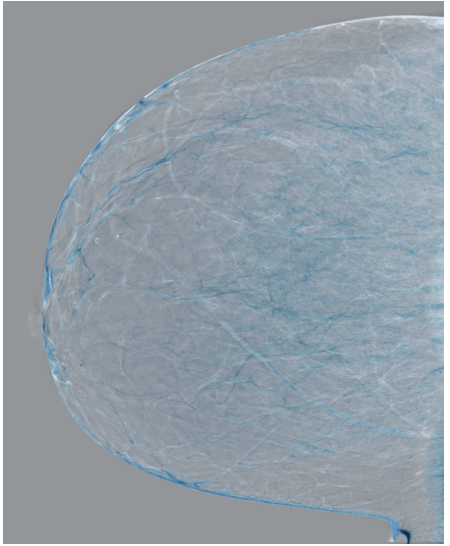

Refer to caption

(a) FeatAlign

(b) FeatAlignReg

(c) ImgFeatAlign/ImgAlign

(d) FeatAlign

(e) FeatAlignReg